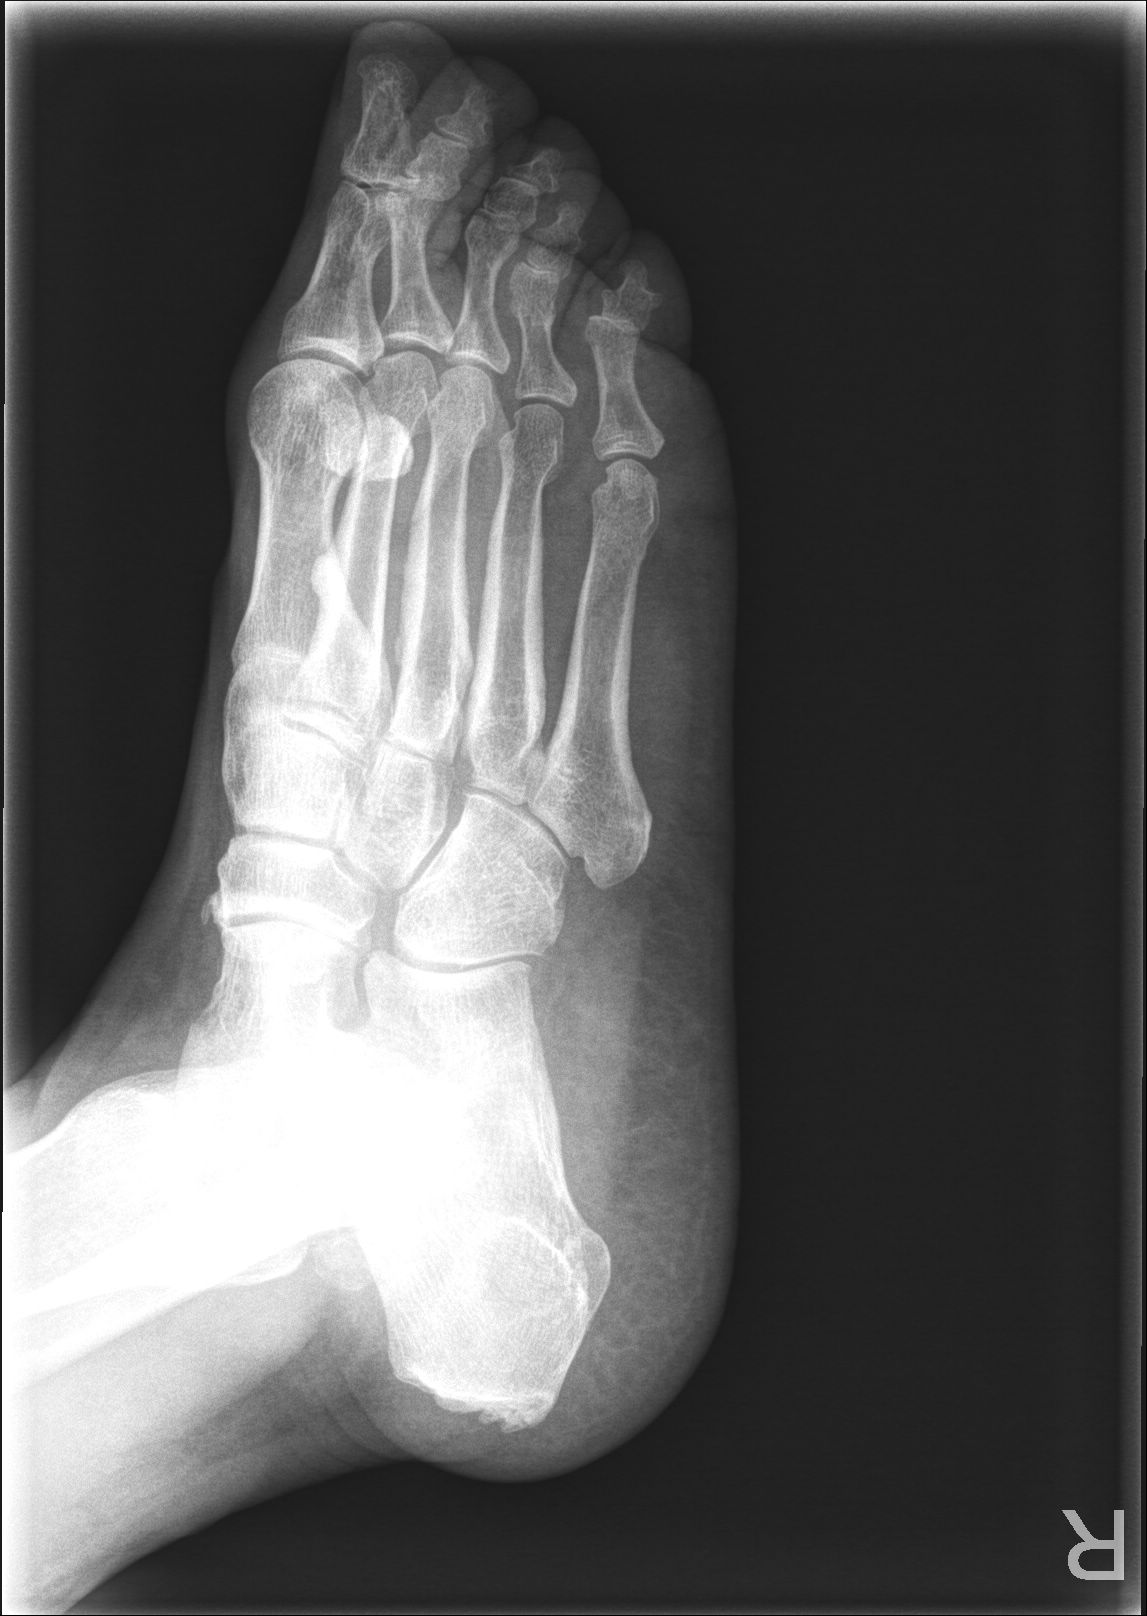

X13619:第二跖旁类圆形高密度影像,求解?在线等! ...

X13619:第二跖旁类圆形高密度影像,求解?在线等!

第二跖旁类圆形高密度影像,求解?

右第二跖骨内侧局限性突起,考虑变异可能。

投照位置不是很理想,骨瘤。

皮质型骨瘤。

骨突,变异。

没事,子骨

考虑正常变异